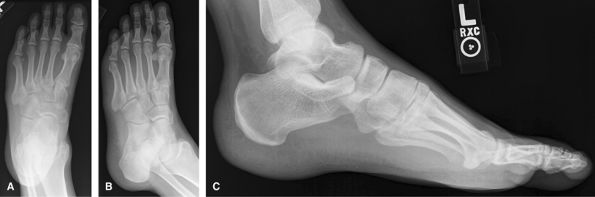

Foot

Perform all 3 views for trauma and nontrauma cases. A

limited 2-view foot is discouraged. Weight-bearing to assess foot

alignment. Non–weight-bearing if painful to stand or looking for a

foreign body or mass. Non–weight-bearing if ulcer and looking for

osteomyelitis. Always remove socks!

Consider US for Morton’s neuroma or plantar fasciitis, or

superficial mass. CT is good for full assessment of Lisfranc injuries.

MRI good for occult fracture or mass.

Figure 20 (A) AP (dorsoplantar). (B) Medial oblique. (C) Lateral (mediolateral projection).